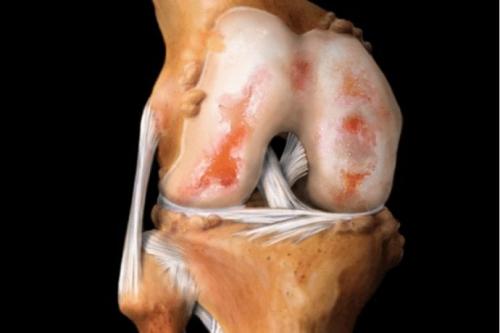

Так выглядит разрушенный хрящ.